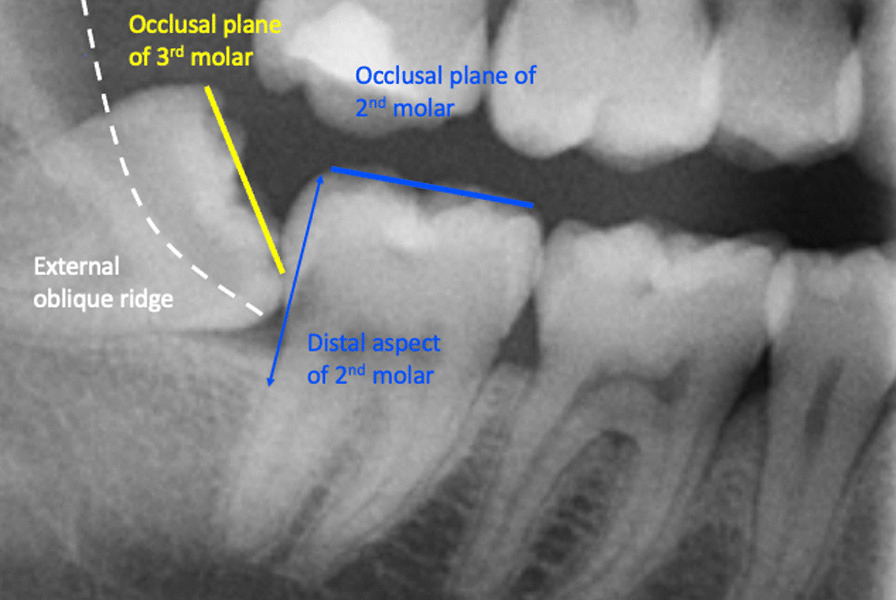

In this study, partial eruption or partial emergence of the mandibular third molar was determined by assessing the third molar position in relation to the adjacent second molar and the anatomical landmarks. The third molars were deemed to be partially erupted when one of the third molar cusps was positioned above the external oblique ridge or the occlusal plane level of the neighbouring second molar. In cases where these anatomical landmarks could not be assessed on the radiograph, the Cementoenamel Junction (CEJ) of the adjacent mandibular second molar in relation to the marginal ridge position of the adjacent third molar was also used to obtain information on the eruption status of mandibular third molars and its depth of impaction. This assessment method is a modified description of the Pell & Gregory classification and class I B, class II B, class III A and B from the original Pell & Gregory categorisation were included [3]. This was applied to all third molar angulation types (mesial, distal, vertical, horizontal and transverse). Figure 1 illustrates an impacted and partially erupted mandibular third molar on a bitewing radiograph contacting the second mandibular molar below the CEJ. Figure 2 shows a section of a panoramic radiograph of a mandibular third molar that was deemed partially erupted. The external oblique ridge or bony anterior border of the ramus that appears radiopaque and is located on the outer aspect of the mandible which runs from the ramus to the first molar is indicated with a white dashed line.

Fig. 2.

Indication of various anatomical points required for the assessment of third molar partial emergence/eruption on a panorama radiograph